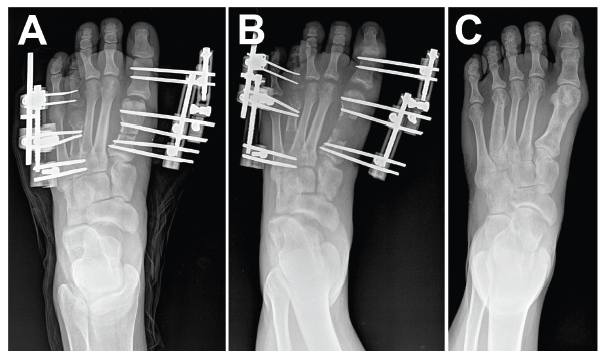

Distraction osteogenesis describes de novo bone production between osteotomy surfaces during gradual bone distraction.1,2 In foot and ankle surgery, these principles can apply to pathology such as: brachymetatarsia, malunion, nonunion, limb length discrepancy, and revision surgery.3-5 In this column we present an updated review of the basics of osteotomy techniques and distraction osteogenesis, including terminology and complications, to improve readers’ understanding of bone lengthening.

Tricortical radiographic consolidation on two orthogonal radiographs mark achievement of bony consolidation. Computed tomography may be necessary to confirm complete osseous healing in foot and ankle cases. Obtaining this endpoint then allows for removal of the external fixation.